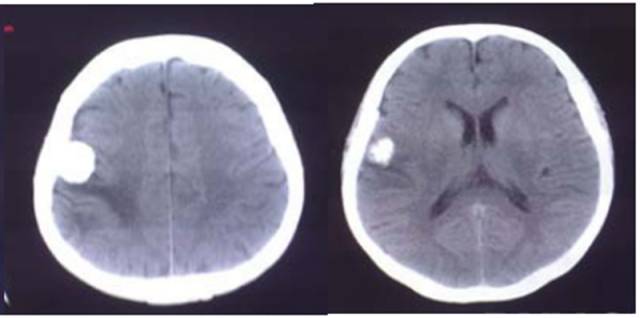

CT平扫(骨窗 脑窗)

病例:男性,30岁,头痛2月

CT平扫